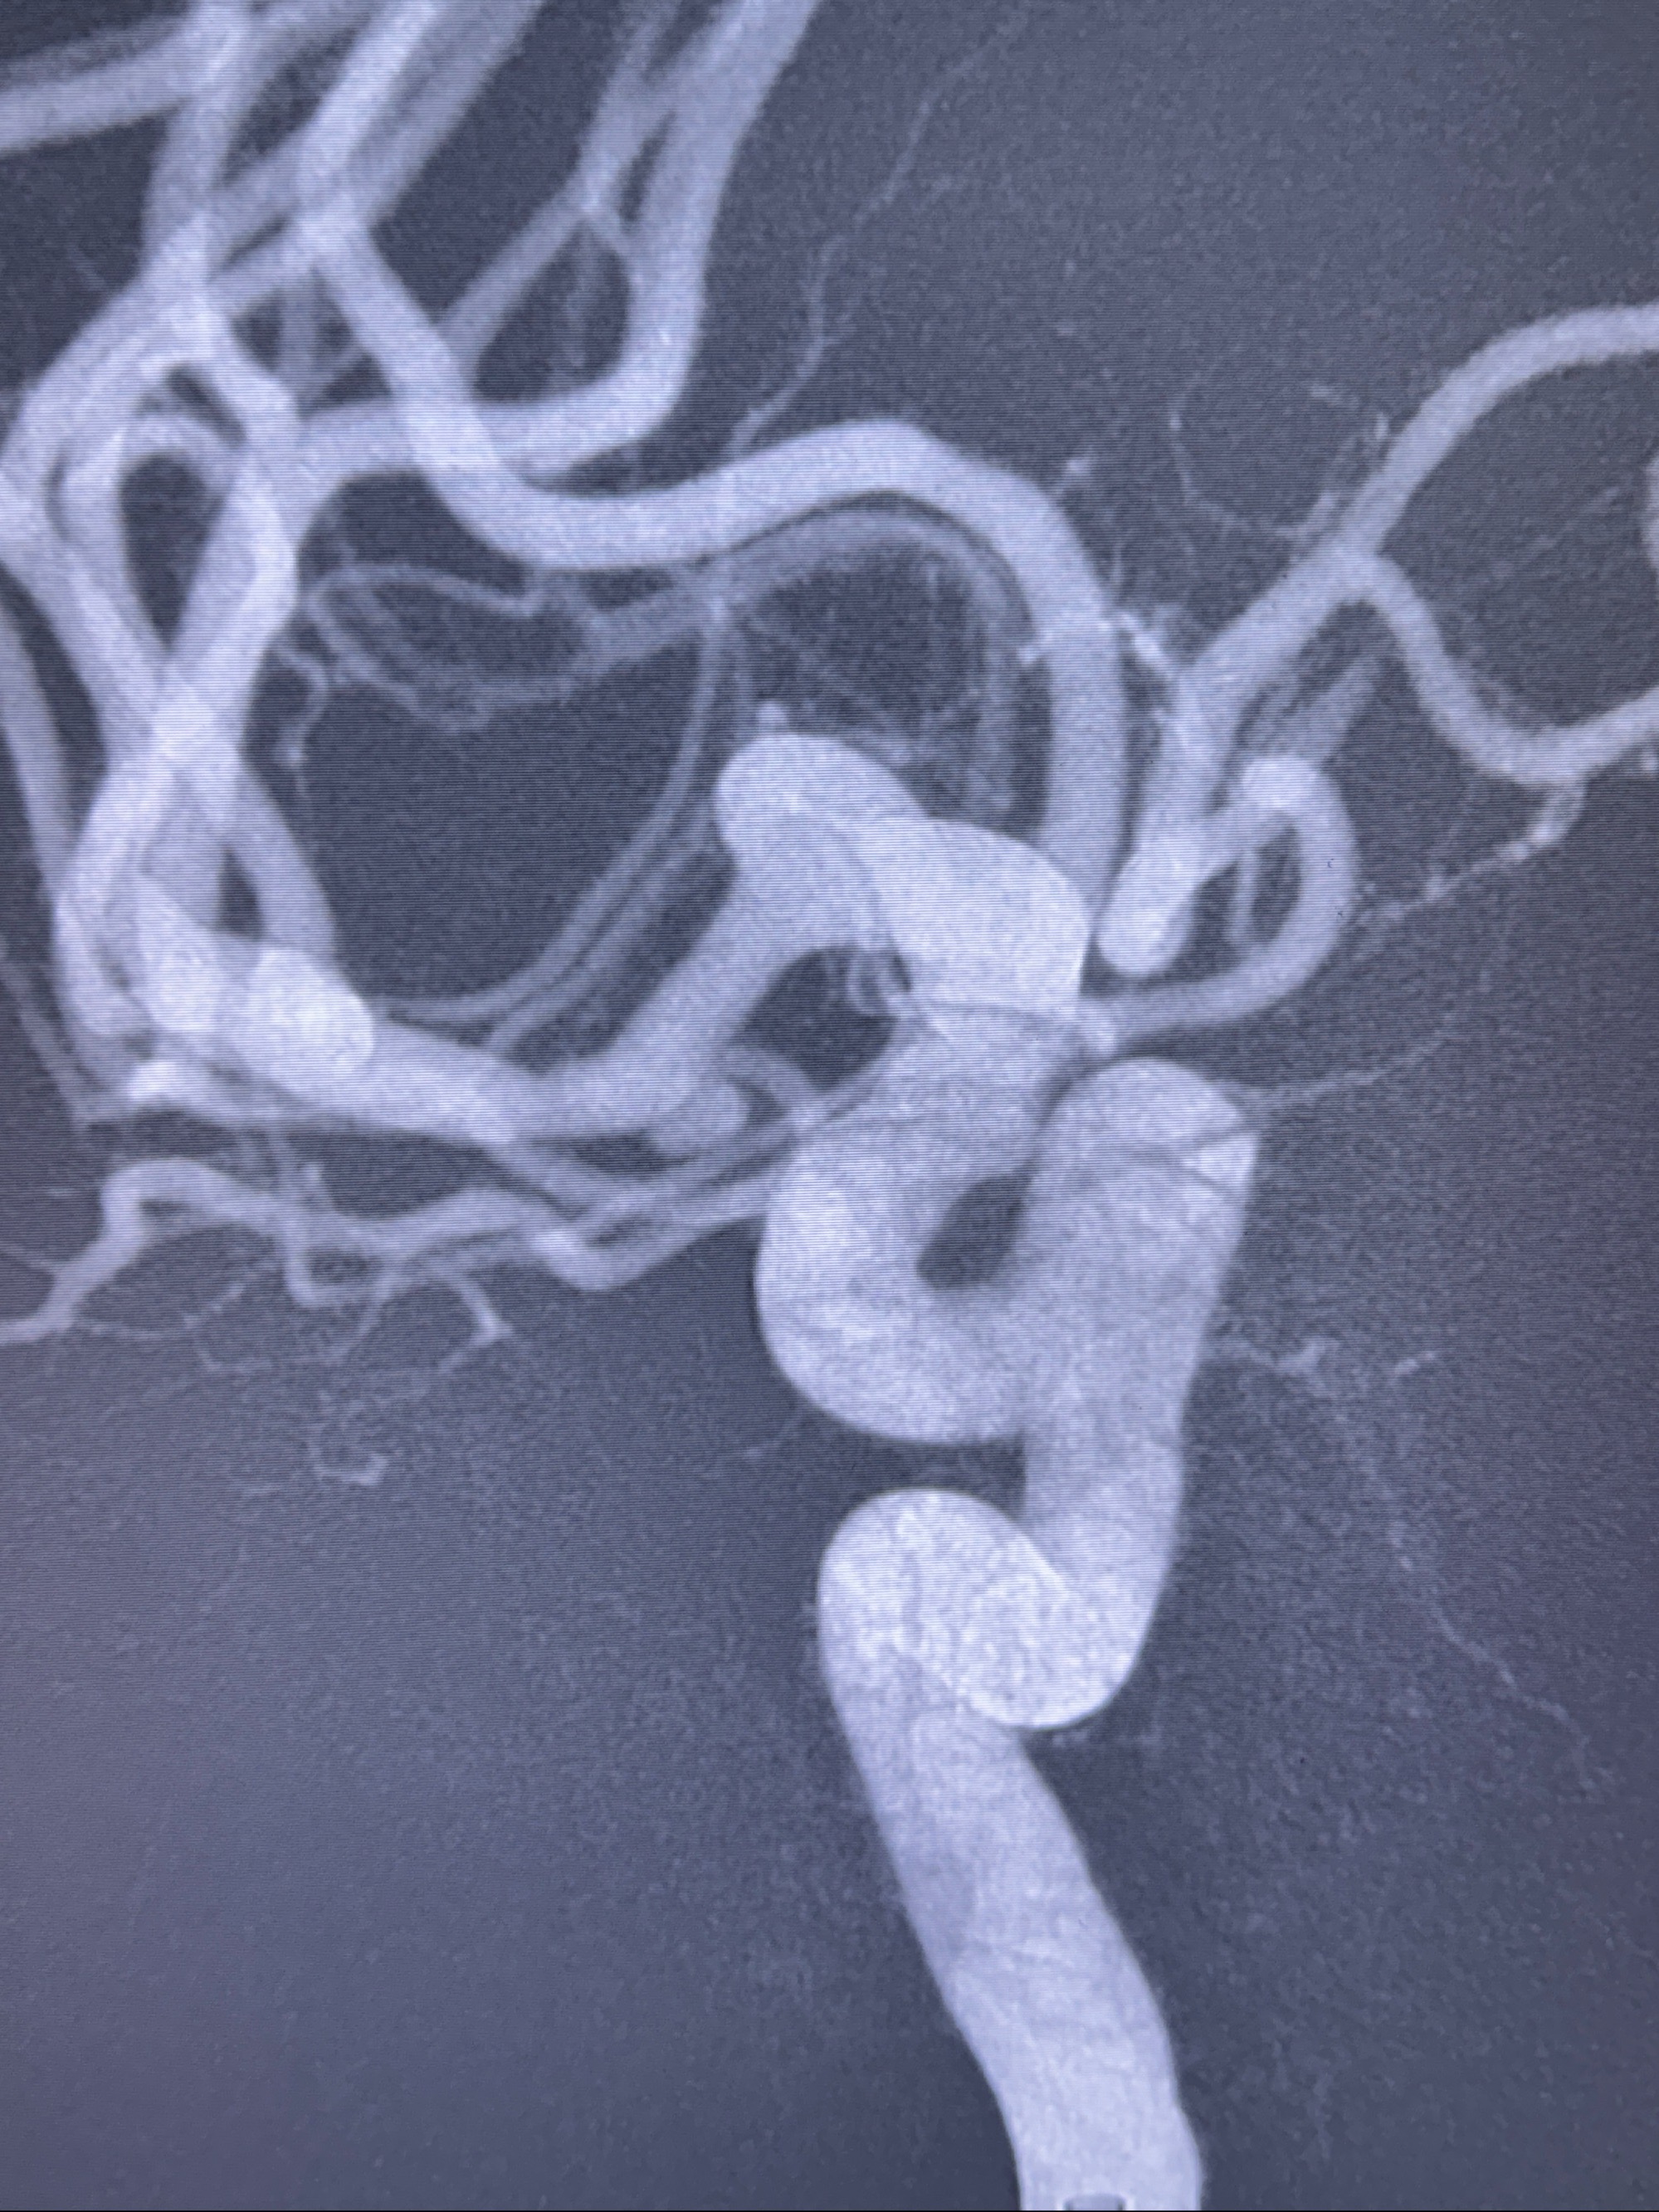

2023-11-24DSA:右侧大脑中动脉下干起始部动脉瘤,约2.3*2.5mm,形态规则

治疗策略:

- 随访?

- 夹闭?

- 单弹簧圈填塞?

- 支架辅助治疗?